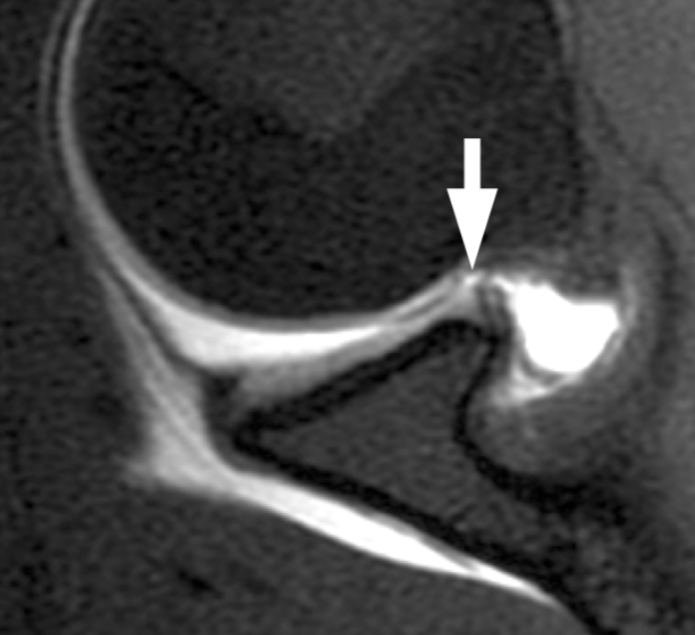

Conocer los hallazgos por imagen de las principales lesiones óseas, ligamentarias, musculares y tendinosas del miembro superior en el ámbito del deporte, así como los mecanismos y principales actividades deportivas que las desencadenan.

Las lesiones del miembro superior son relativamente frecuentes en el ámbito del deporte. El hombro, el codo, la muñeca y la mano son regiones anatómicas con gran movilidad y por tanto muy expuestas a lesiones óseas, ligamentarias y músculo tendinosas como resultado de la actividad deportiva.

El hombro y el codo se afectarán con relativa frecuencia en deportes que impliquen un lanzamiento o actividad por encima de la cabeza. En el caso de la muñeca y mano son habituales las lesiones por contacto directo o caída con la mano en extensión.